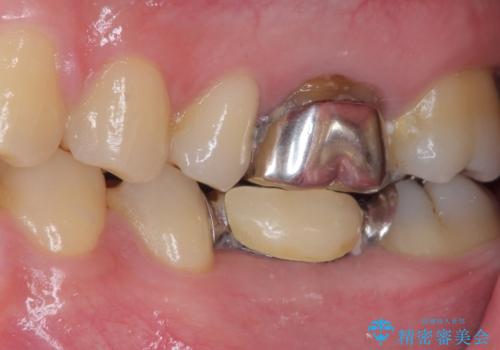

- 外れやすい銀歯をやり替えたいと来院された患者様です。

他院にて治療したインレーブリッジが何回か外れてつけ直しを繰り返しているため、外れないようにしてほしいとのことでした。

できるだけ外科処置は避けたいという患者様の希望と、すでにブリッジの土台となる両隣の歯を削って治療していることを考慮し、患者様と相談の上、今回はインプラントではなくフルジルコニアブリッジで治療することとしました。